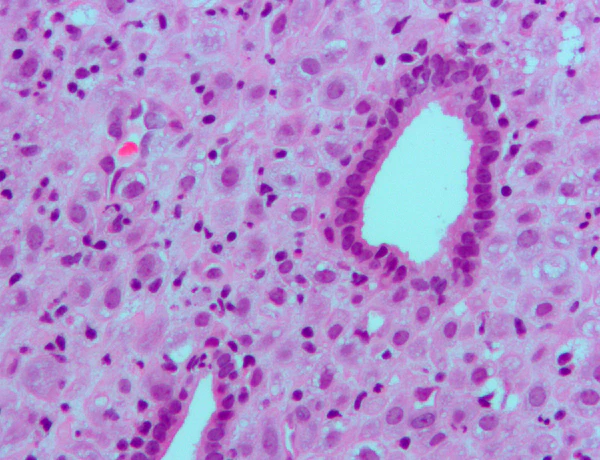

- Прогестерон переводит эндометрий в секреторную стадию, чтобы подготовить матку к имплантации. В то же время прогестерон влияет на эпителий влагалища и слизь шейки матки, делая ее густой и непроницаемой для сперматозоидов. Прогестерон обладает антимитогенным действием в эпителиальных клетках эндометрия и уменьшает тропные эффекты эстрогена. Если беременность не произошла, уровень прогестерона уменьшится и произойдёт менструация. Нормальные менструальные кровотечения происходят из-за падения уровня прогестерона. Если овуляция не происходит и жёлтое тело не образовывается, уровень прогестерона может быть низким, приводя к ановуляторным дисфункциональным маточным кровотечениям.